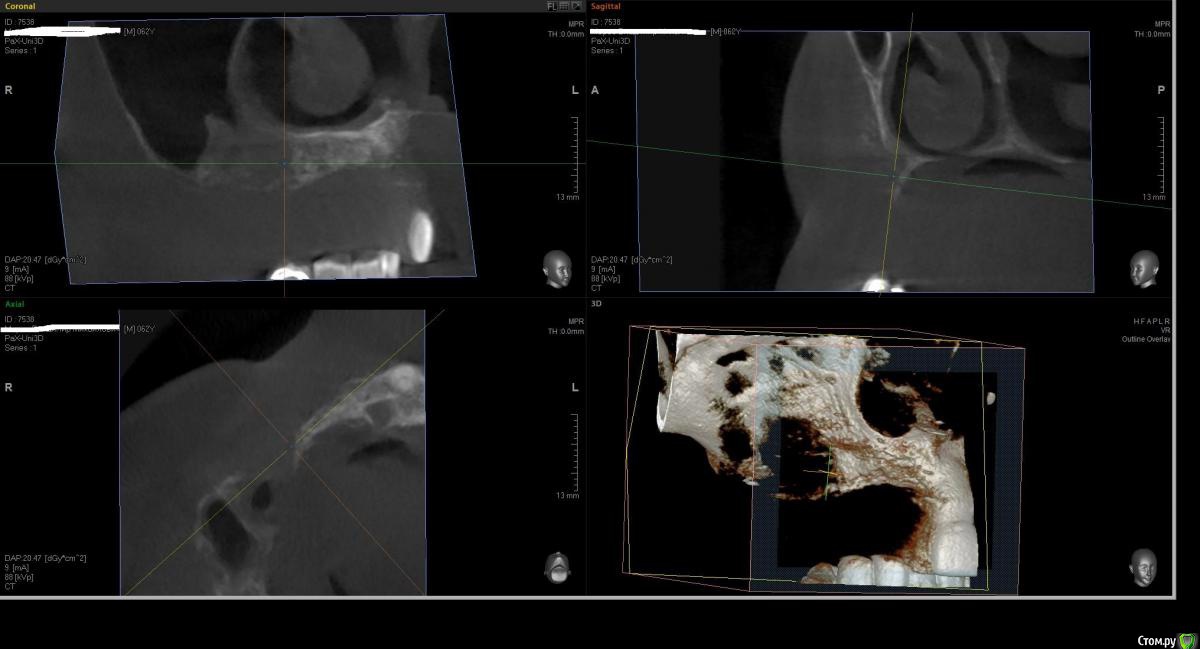

Kostoprav Опубликовано 1 августа, 2016 Поделиться Опубликовано 1 августа, 2016 что бы вы сделали в данной ситуации уважаемые коллеги? был синус и титановая сетка во фронте но увы все прокисло ((( 1 Ссылка на комментарий

Kostoprav Опубликовано 2 августа, 2016 Автор Поделиться Опубликовано 2 августа, 2016 Всё вычистить, подождать заживление и повторить.это кт уже после чистки, а повторить снова титановой сеткой?думаю снова сетка здесь не прокатит( Ссылка на комментарий

Kostoprav Опубликовано 3 августа, 2016 Автор Поделиться Опубликовано 3 августа, 2016 скисло через 3 мес, до этого все было идеально!но меня больше беспокоит вопрос что теперь с этим делать, там теперь кости особенно во фронте почти нет.какую технику использовать? Ссылка на комментарий

Kostoprav Опубликовано 3 августа, 2016 Автор Поделиться Опубликовано 3 августа, 2016 Меня не удивляет что резорбировался графт под сеткой. Но где тут графт в пазухе? Что там было с синуслифтингомначалось все как раз из синуса. пазуха разделена перегородкой, я поднял дно только в передней камере Ссылка на комментарий

Bier Опубликовано 8 августа, 2016 Поделиться Опубликовано 8 августа, 2016 Зигомы... 1 Ссылка на комментарий

kriokov Опубликовано 9 августа, 2016 Поделиться Опубликовано 9 августа, 2016 Зигомы...х\з , там по их по две с каждой стороны надо, если только на зигомах ( фо фронте с костью жиденько)но если опыт работы с ними есть - то вариант Ссылка на комментарий